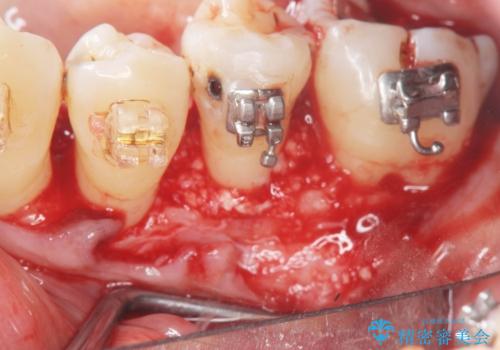

歯周病再生治療と歯周ポケット除去 歯周外科手術

- 他院で歯周病を指摘され、様子見ではなく根本的な治療はないか?とご相談に来院されました。

重度の歯周病で再生療法の適応ではない最後方臼歯は抜去行い、インプラント治療、

がたつきの強い天然歯を矯正治療で整えたのち、再生治療、歯周ポケットを除去する歯周外科手術を行いました。